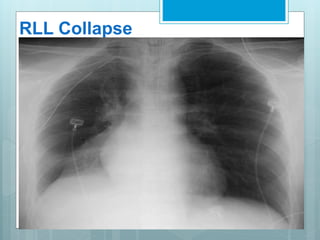

RLL Collapse

 Collapse is in post, med & inf

direction.

 Major fissure swings down

&backward.

 Hilum is displaced inferiorly.

 Hemidiaphragm is elevated.

 On PA view a triangular opacity

adjacent to spine with base on

hemidiaphragm.

 On lateral view there is

increased opacity over lower

thoracic vertebrae .

 Another indirect sign is vascular nodular sign, due to

compensatory hyperinflation of upper lobe.

 Radiographically seen as "hair-pin" turning of vessels &

"too-many nodules" along cardiac margin, which are end-on

vessels.